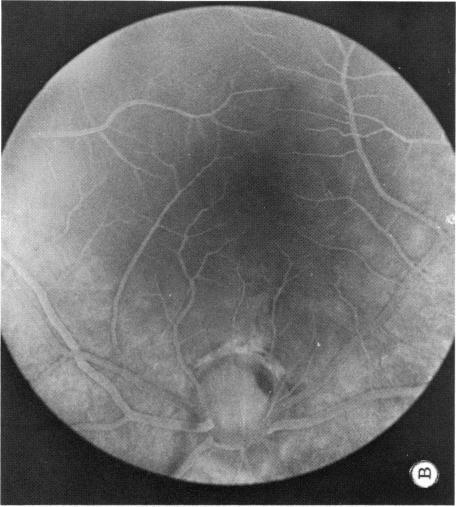

Six cases of congenital pit of the optic nervehead associated with posterior serous retinal detachment are presented. All were treated by photocoagulation along the disc margin in the area of retinal detachment. In five cases reattachment of the retina occurred, after the clinical development of a film chorioretinal adhesion at the disc margin, and appeared to be secondary to the treatment. The sixth case (Case 4), although treated, appeared to represent a spontaneous reattachment. This disorder, which frequently results in permanent decrease of central vision, affected the better, or only, eye in two of the six cases herein reported. Fluid, probably from the vitreous cavity, appears to gain access to the subretinal space via the pit. Reattachment in treated cases occurred only if an effective chorioretinal adhesion was created over the entire area of the fistulous detachment at the disc margin. Field defects after treatment appear to be secondary to either the optic pit itself or the longstanding retinal detachment, oftern accompanied by pigmentary degeneration and cystic macular degeneration, rather than juxtapapillary photocoagulation treatment.

本文报告6例先天性视神经乳头凹合并浆液性视网膜脱离。所有病例均采用视网膜脱离区域沿视盘边缘光凝治疗。5例视网膜脱离在视盘边缘形成脉络膜视网膜粘连后复位,似乎是治疗的继发结果。第6例(病例4)虽经治疗,但似乎是自发复位。这种疾病常导致中心视力永久性下降,在本文报告的6例中有2例影响了较好或仅有的一只眼。液体可能来自玻璃体腔,似乎通过视神经乳头凹进入视网膜下间隙。治疗病例中,只有在视盘边缘瘘管性脱离的整个区域形成有效的脉络膜视网膜粘连时,视网膜才会复位。治疗后的视野缺损似乎继发于视神经乳头凹本身或长期视网膜脱离,常伴有色素性变性和黄斑囊样变性,而非视盘旁光凝治疗。